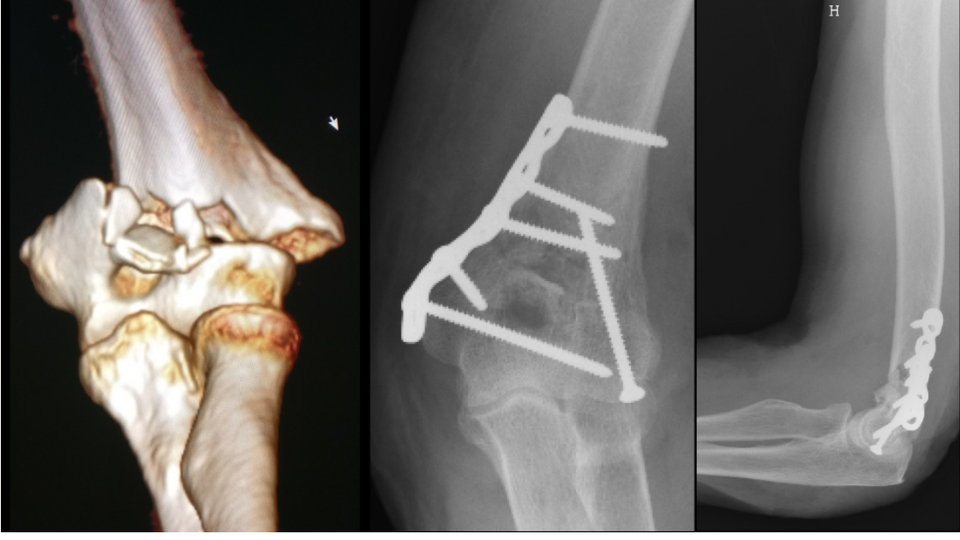

Fractures du COUDE Fractures distales de l humérus Fracture Coude Traitement La fracture du coude désigne le plus souvent la fracture de la parte inférieure de l’humérus, qui est l’os du bras. Le traitement des fractures de l’olécrane repose sur le port d’une attelle, parfois une chirurgie et un traitement par antibiotiques en cas de fracture. Une fracture du coude est une rupture d’un ou plusieurs des os qui constituent l’articulation. Fracture Coude Traitement.

fracture coude face Docteur Touchard Fracture Coude Traitement Le traitement des fractures de l’olécrane repose sur le port d’une attelle, parfois une chirurgie et un traitement par antibiotiques en cas de fracture. Les fractures de types i et ii ne nécessitent généralement pas de chirurgie, un traitement orthopédique pourra être suffisant. Selon l’os qui est fracturé, et donc la localisation de la fracture, le nom précis de la. Fracture Coude Traitement.